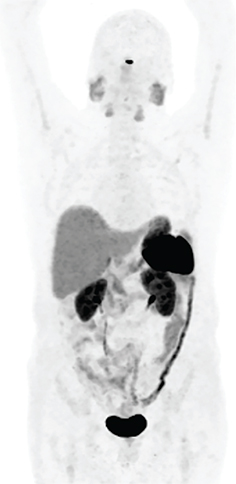

Radiation safety precautions after receiving 177Lu-DOTATATE therapy

Radiation safety precautions for patients after receiving 177Lu-DOTATATE therapy are to restrict the dose received by patients’ family members to less than 5 mSv in 5 years and to members of the public to less than 1 mSv per year. Patients receive oral and written radiation safety precautions for three days after receiving therapy. Blood and urine are the main sources of contamination during and after radionuclide administration. 177Lu-DOTATATE is excreted primarily in urine, therefore, the foremost focus for the first 3 days after therapy is to prevent urinary contamination (46). During this time, a double flush of the toilet is recommended after urination. Patients should wash their hands after using the bathroom. The RADAR website has an online tool that allows the calculation of cumulative doses to family members or members of the public from exposure to patients treated with 177Lu-DOTATATE (47). In addition to the beta particles, 177Lu-DOTATATE also emits two gamma rays (113 KeV and 208KeV) with low relative abundance (6.2% and 10.4% respectively) (48) (Figure 5).

Fig 5

Figure 5. 74-year-old female with advanced and inoperable metastatic ileal NET. A. 68Ga-DOTATATE MIP image and B. Fused coronal image show multiple intensely somatostatin receptor-rich tumors in the liver and portocaval lymph node. C. Post-therapy emission scan acquired 7 days after 117Lu-DOTATATE therapy (anterior and posterior images) Somatostatin receptor rich tumor in liver and a portocaval lymph node.